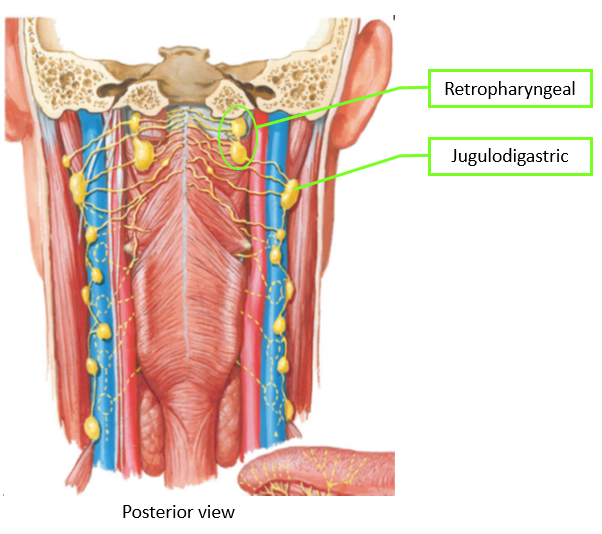

Lymphatic system

總圖

Nodes

Groups

- Level I

- the submental group (Ia), and the

submandibular group (Ib). - Level II

- the upper jugular lymph nodes

- level IIa – CN XI 前

- level IIb – CN XI 後

- Level III

- the middle jugular lymph nodes

- Level IV

- the lower jugular lymph nodes

- Level V

- all lymph nodes contained within the posterior triangle

- Level VI

- lymph nodes of the anterior (central) neck compartment